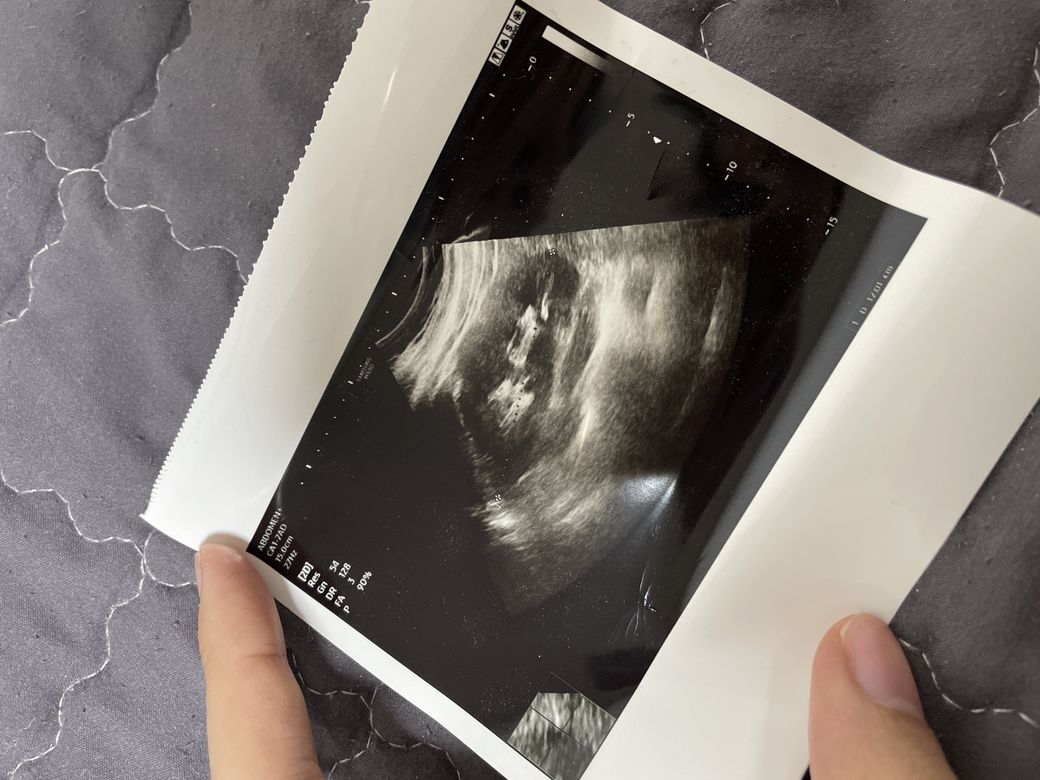

아기 초음파 사진인가요??맞다면 몇주인가요?

아니면 다른장기를 초음파로 찍은건가요??

일반적으로 초음파는 사진에 어떠한 장기를 확인하였는지 레이블링을 하여야 정확하게 알 수 있지만 장기의 생김새로 보아서는 아기에 대한 초음파는 아닐 것으로 생각되며 신장을 촬영한 사진으로 보입니다.